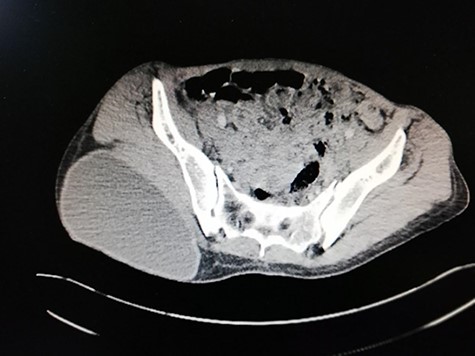

Abdominal ultrasound delineated multiple cystic lesions in the liver and the spleen. Computed tomography (CT) scan showed up to six rounded homogenous low-density cysts in both lobes of the liver, ranged from 0.15 to 0.17 m, and one large cyst in the spleen, containing multiple peripheral small vesicular cysts (Fig. 1). CT scan showed a 0.03 × 0.07 m cyst in the upper mediastinum, adjacent to the aortic arch (Fig. 2A); two rounded well-defined homogenous cysts in the lower lobe of the left lung, measured 0.17 × 0.17 m, and in both breasts (Fig. 2B and C) and a single large 0.2 × 0.13 m oval homogenous cyst above the right gluteal muscles (Fig. 3).

Abdominal CT scan reveals: six rounded homogenous low-density cysts in the liver, measuring from 0.15 to 0.17 m. A large rounded cyst in the spleen, containing multiple peripheral small vesicular cysts.

Pelvic CT scan reveals: a large oval homogenous cyst, above the right gluteal muscles, measuring 0.2 × 0.13 m.